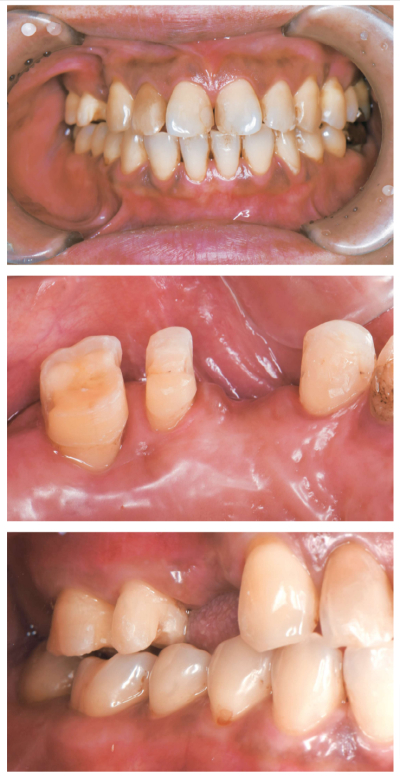

45 歳の女性。右側の咀嚼困難を主訴として来院した。1年前に上顎右側第一小臼歯と第二大臼歯を齲蝕のため抜去したという。検査の結果、⑥⑤4③⏌のブリッジを製作することとした。支台歯形成後の口腔内写真を別に示す。

咬合採得について適切なのはどれか。3つ選べ。